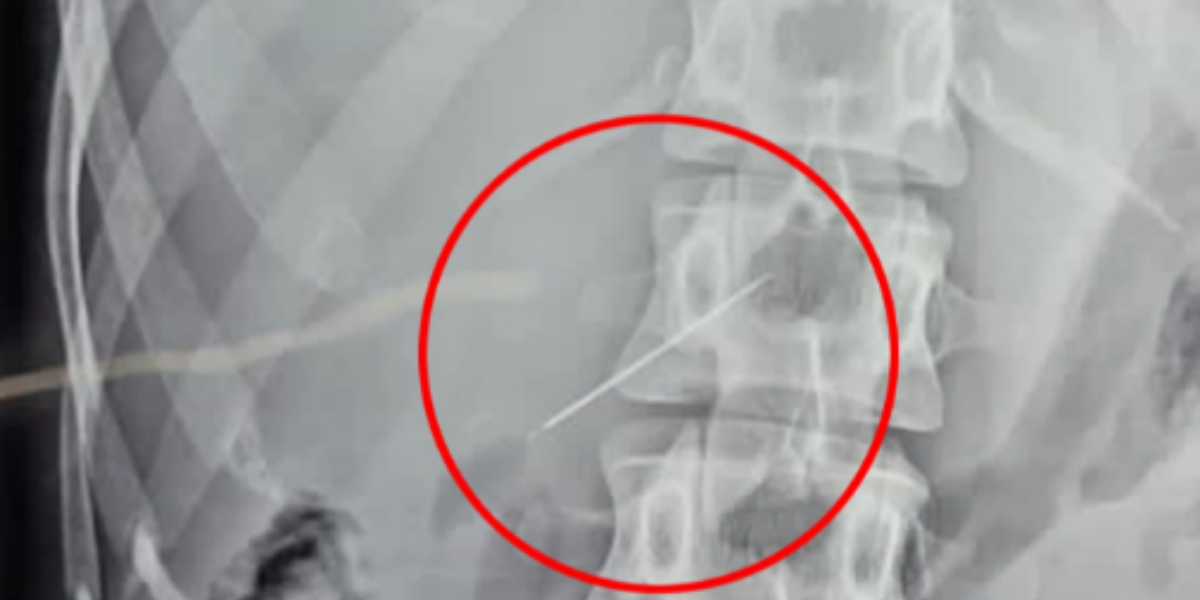

After getting a sewing needle stuck in her teeth and swallowing it, a woman battled to breathe. The moment doctors removed the little object during emergency surgery is captured on shocking photo.

After being returned home after 10 days of several tests, including sonography, endoscopy, X-rays, and CT scans, a final ultrasound discovered the tiny needle embedded in her liver.

She was hurried into surgery once the needle was discovered to remove the object that was causing her anguish.

According to Jam Press, the procedure to remove the needle took two hours and utilised keyhole surgery, which requires only a small opening.